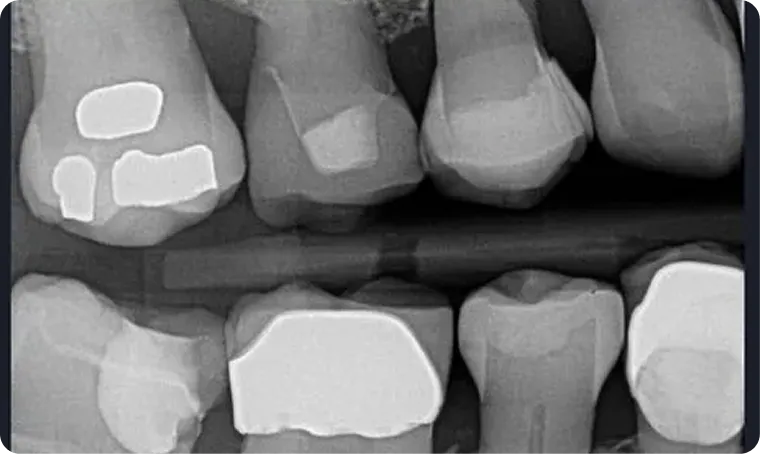

AI without findings

AI activated, showing Decay in red, and Yellow lines indicate bone loss